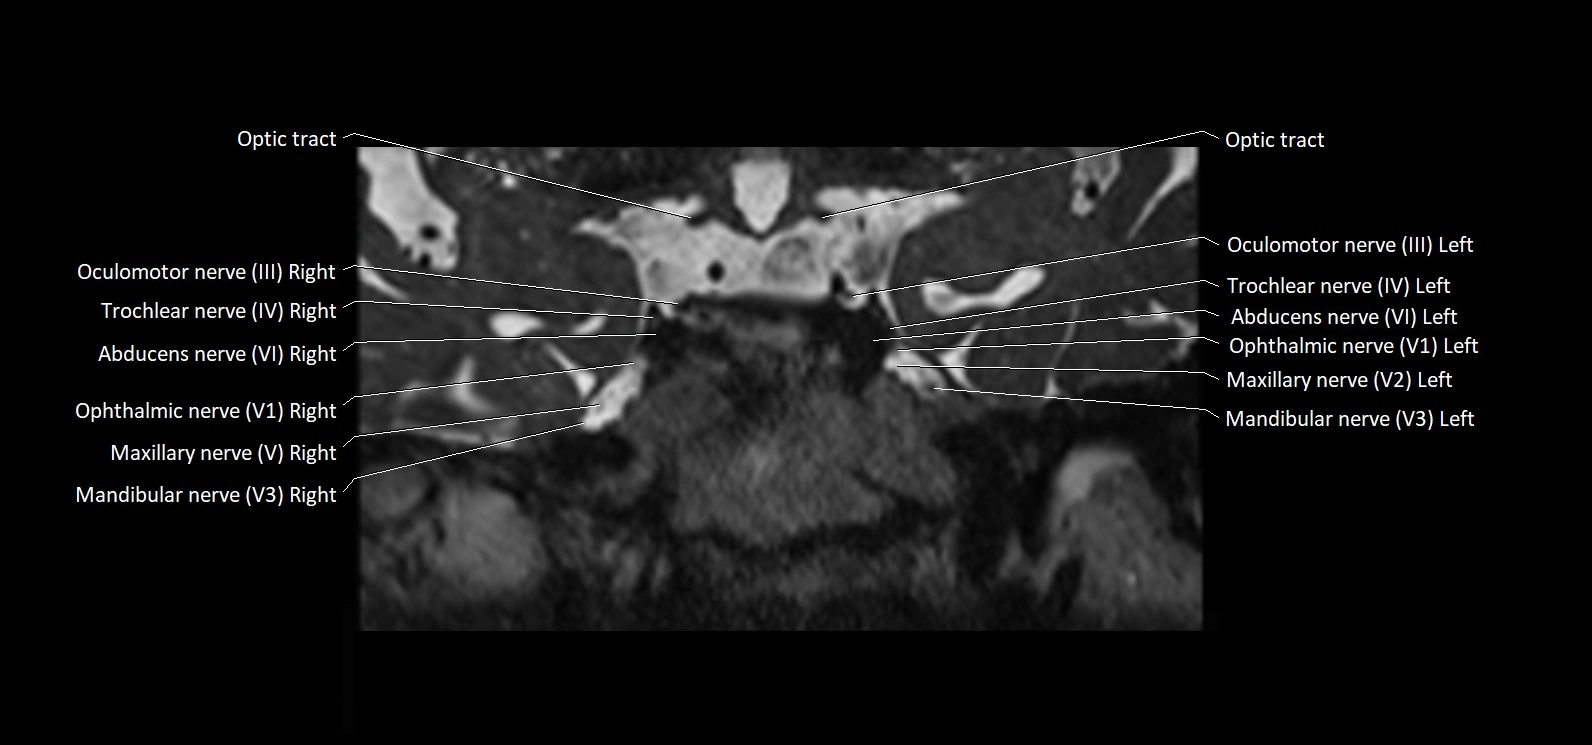

MRI images

image